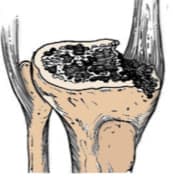

Ясыг тайрахдаа хавдрын ирмэгээс 2 см зайд тайралт хийсэн, нийт 6 хавдартай тохиолдолд хавдар дахисан хүндрэл гараагүй. Хоёрдогч мэс заслын үед шилбэ ясны дутмагшлыг Anderson Orthopaedic Research Institute (AORI) (Engh & Ammeen, 1999) ангиллаар ихэвчлэн ангилдаг.

Үе дайрсан ясны анхдагч хавдар, ясны дутмагшлын үед хийгдэх мэс засалimage12

Зураг 1. Дунд чөмөг ба шилбэ ясны I зэргийн дутмагшил